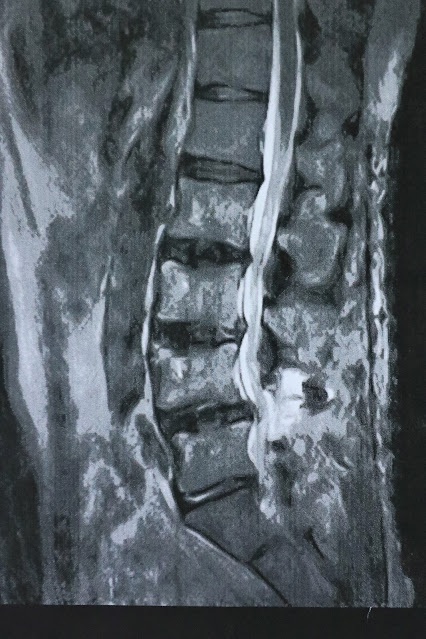

手術前10月4日のレントゲン 4~5間が特にひどく、すべり症&狭窄症

術後8月18日のレントゲン写真 脊柱管狭窄症が改善 下肢のしびれが消えました